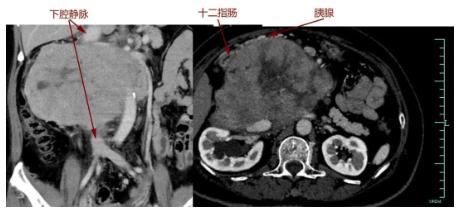

很快,吴女士转院至浙大一院肿瘤外科,完善各项术前检查后,滕教授发现情况远比最初判断严重:肿瘤与胰十二指肠、肾脏等多个脏器及主干血管关系不清,直接吞噬了腔静脉,双肾血管受累,已有轻度肾功能异常。

“我们做过很多类似的手术,但像她这样与血管黏连这么牢的很少。”滕教授表示,随即组织了放射科、泌尿外科、血管外科、肛肠外科、麻醉科、输血科等进行会诊,制定严密的手术方案。针对术中血管与脏器保留或重建的关键问题,他与肛肠外科主任、小肠移植专家吴国生教授,血管外科主任张鸿坤进行了反复探讨,“肿瘤吞噬了腔静脉,这是人体最重要的血管,就像下水管一样,稍有不慎就会大出血,造成不可挽回的后果,而肿瘤如果侵犯肠系膜,可能还要做自体小肠移植。”

手术过程和预计的一样凶险,手术团队小心翼翼将肠道、肾脏血管从肿瘤成功分离。但真正的困难很快出现:肿瘤与胰腺头部黏连,下腔静脉也被侵犯,滕教授当机立断,切断十二指肠及胰头,游离肿瘤两端下腔静脉,最后分离切除大血管部分肿瘤。由于肿瘤向血管内生长,肿瘤切下的同时血液一涌而出,早有准备的团队立即阻断下腔静脉以控制出血,快速切除肿瘤,张鸿坤主任随即缝合修补下腔静脉。万幸的是,术中发现肿瘤与肠系膜血管黏连不严重,避免了自体小肠移植。